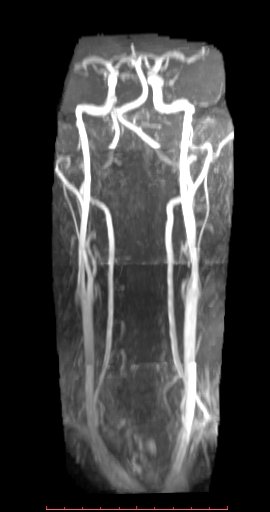

白色文字(排除指定关键词) Imaging Anatomy: interactive PACS-like atlas of radiological anatomy

解剖学模块